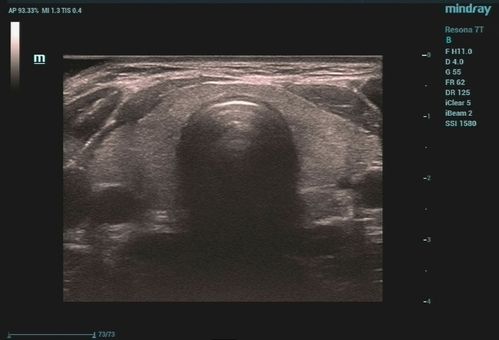

甲状腺超声

甲状腺超声,甲状腺超声图像

教你正确解读甲状腺超声的7种常见影像

超声入门正常甲状腺超声表现

常见甲状腺疾病的超声诊断:解剖,声像图及正常值

甲状腺超声图像

甲状腺超声测量示意图

甲状腺超声正常值

甲状腺超声诊断

甲状腺结节超声

甲状腺超声标准测量图

甲状腺超声解剖

甲状腺超声报告